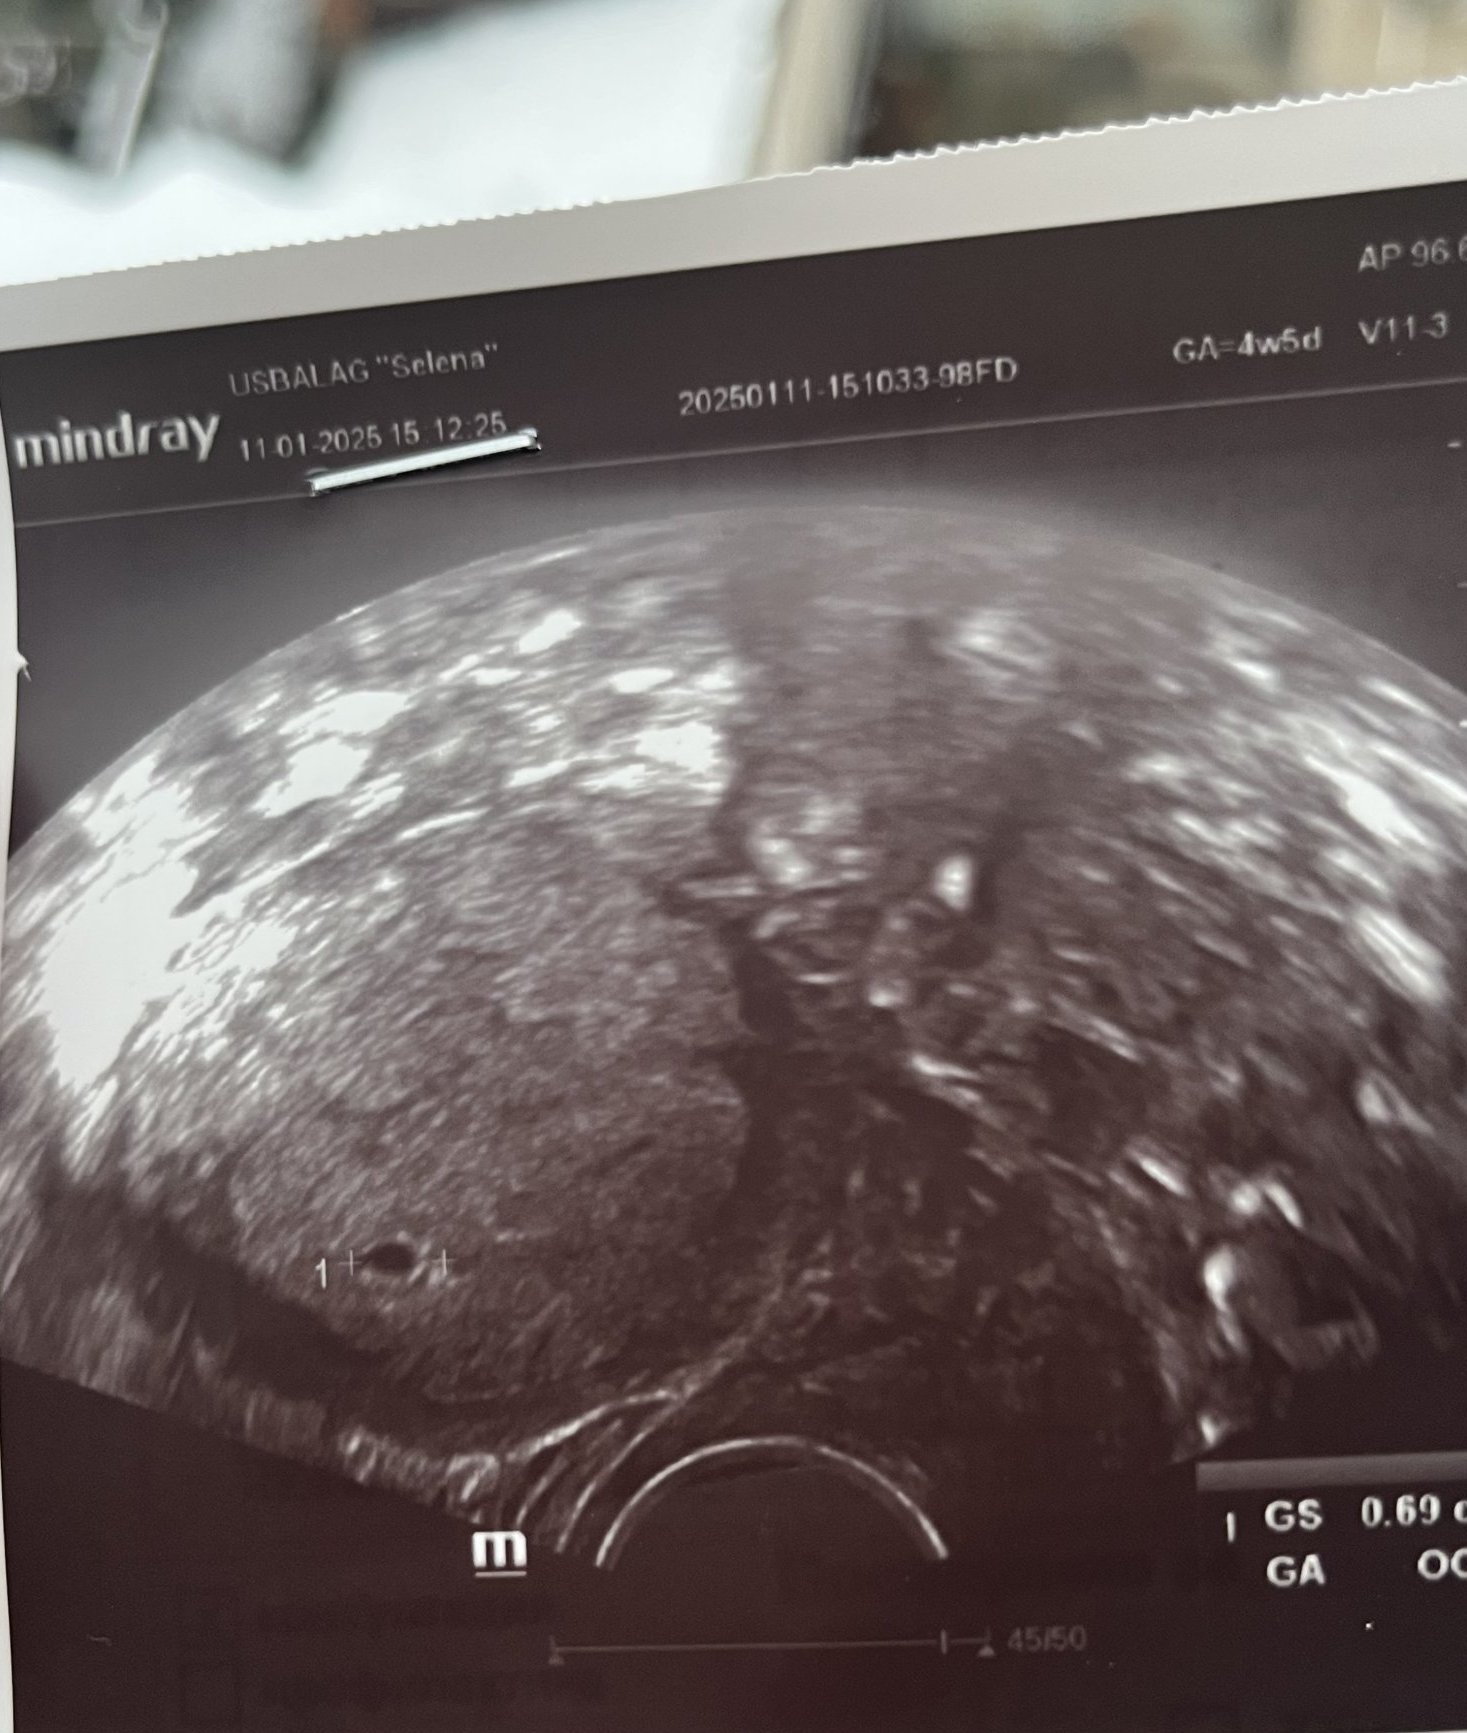

Какво представляват белите точки в плодния сак на ехографската снимка?

Какво представлява жълтото тяло на ехографската снимка?

Какво представляват черните точки в матката на ехографската снимка?